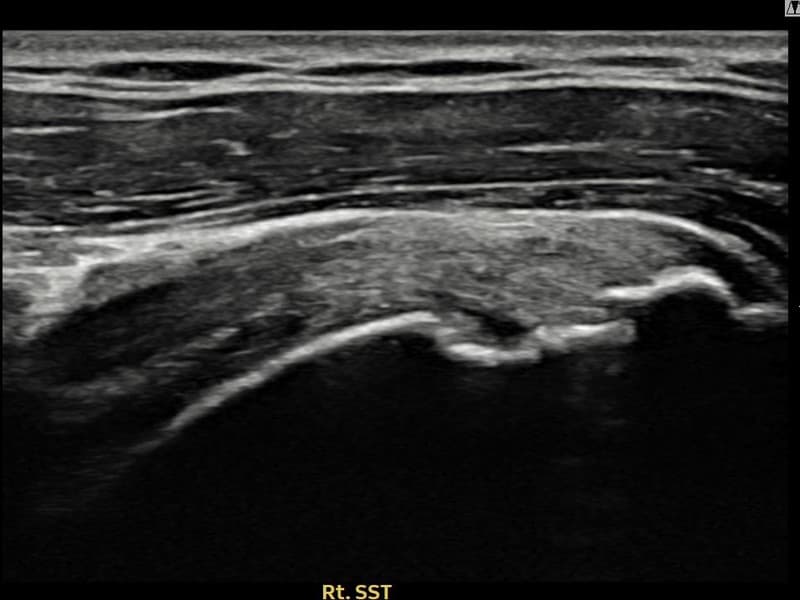

术后

术前超声确认右侧 冈上肌腱 滑囊面侧部分撕裂,右侧冈上肌腱回声不连续伴肌腱缺损(13mm × 6mm (肌腱厚度约62%缺损))。术后超声显示撕裂部位充满再生组织,肌腱连续性恢复,回声模式正常化。

该患者持续肩痛。详细超声检查确认右侧 冈上肌腱 滑囊面侧部分撕裂(缺损:13mm × 6mm (肌腱厚度约62%缺损))。在超声引导下实施非手术缩小缝合术。术后佩戴支具约4-6周,随后进行分阶段康复锻炼。随访超声确认肌腱连续性恢复、结构稳定,患者顺利回归日常生活。